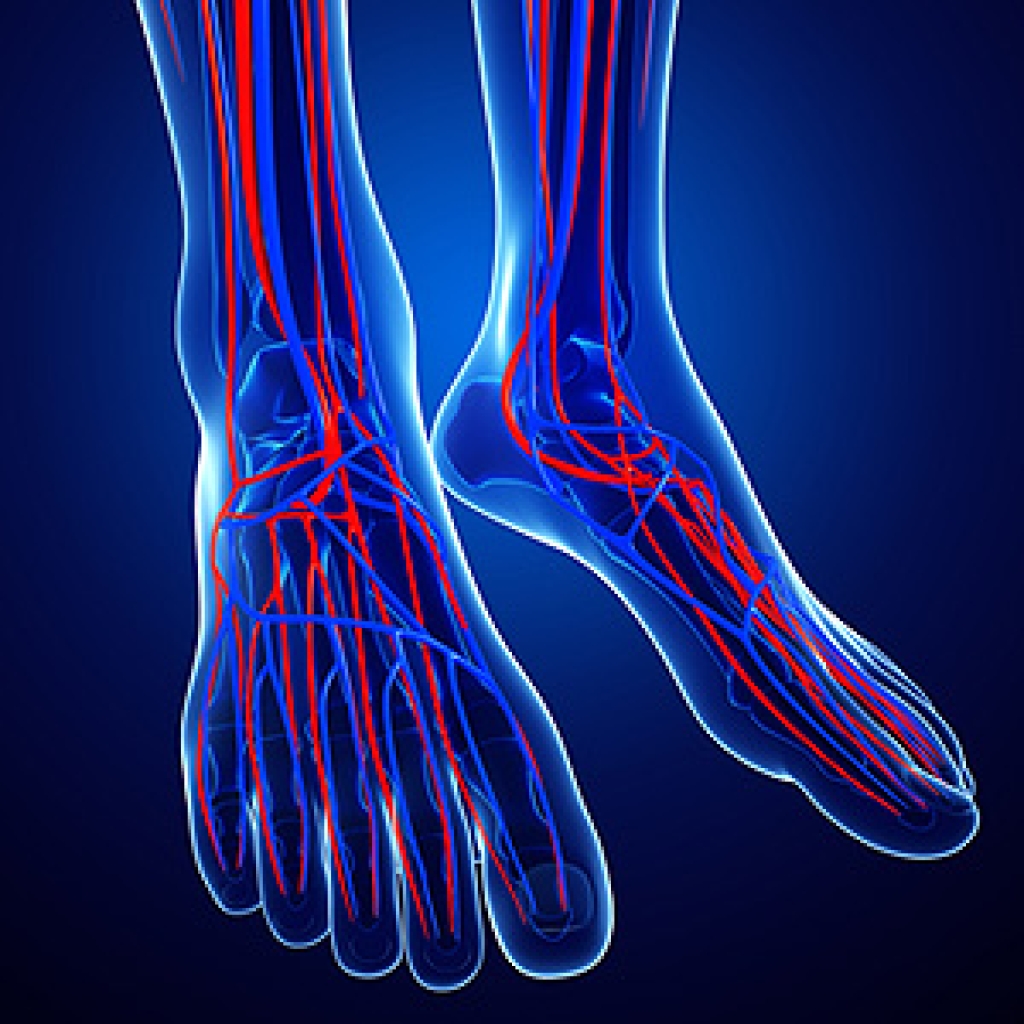

- Increased blood flow to the tendon

The Achilles tendon is a tendon that connects the lower leg muscles and calf to the heel of the foot. It is the strongest tendon in the human body and is essential for making movement possible. Because this tendon is such an integral part of the body, any injuries to it can create immense difficulties and should immediately be presented to a doctor.